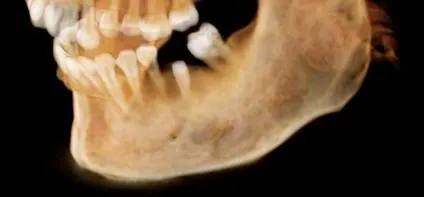

Case 1